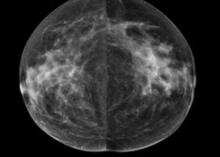

http://glossary.itnonline.com/3d-mammographyHologic Inc. announced that a groundbreaking new study published in Radiology, the Radiological Society of North America scientific journal, found that the addition of three dimensional (3-D) mammography (breast tomosynthesis) screening technology to a 2-D breast screening exam significantly increased cancer detection while reducing the number of false positives.

According to a new market research report "Breast Imaging Technologies Market (Digital Mammography,3D Breast Tomosynthesis, Breast MRI, Breast Ultrasound, Molecular Breast Imaging, Optical Imaging, PET/CT/PEM Modalities) Technology and Market Analysis & Global Forecasts to 2017" is an attempt to showcase the market impact of current and emerging breast imaging technologies having excellent growth potential in the coming five years. The technologies profiled in the report are segmented into Ionizing breast imaging modalities and Non-Ionizing breast imaging technologies on basis of radiation. Ionizing breast imaging modalities include Mammography, 3D Breast Tomosynthesis, Cone beam Computed Tomography (CBCT), Positron Emission Mammography (PEM), Molecular Breast Imaging (MBI), Positron Emission Tomography (PET) and Breast Specific Gamma Imaging (BSGI). The various Non-ionizing modalities for breast screening covered in the report are Breast MRI, Optical Imaging, Breast thermography and Breast Ultrasound.